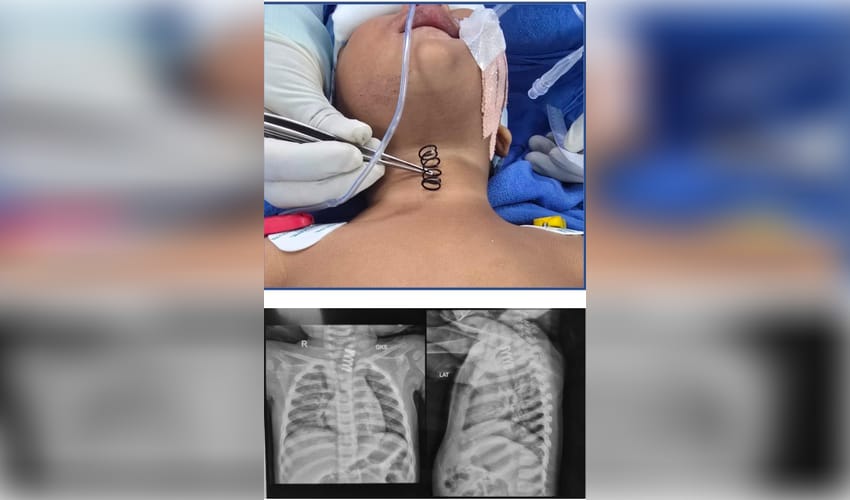

“During the examination, an X-ray revealed a large metal spring lodged in the upper part of the child's oesophagus,” AIIMS said, "with ulcerations extending along the mucosa".

“The spring was stuck on the upper part of the food pipe. And the thickness of the spring was much more than the normal spring, which we see in our pens. It was approximately half an inch wide and at least 1.5 to 2 inches long,” Professor Dr. Vishesh Jain, from the Paediatric Surgery Department, told AHN.